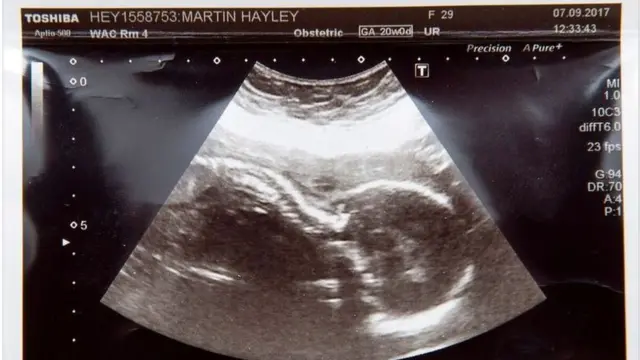

По итогам УЗИ на сроке в 20 недель врачи сообщили Хейли Мартин, что у ее ребенка редкое врожденное заболевание - двусторонняя агенезия почек, что означает, что ребенок либо родится мертвым, либо погибнет спустя несколько минут после рождения.